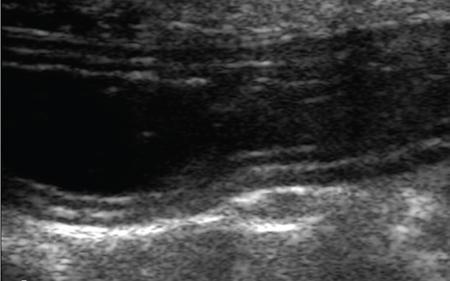

Ultrasonography in small bowel imaging